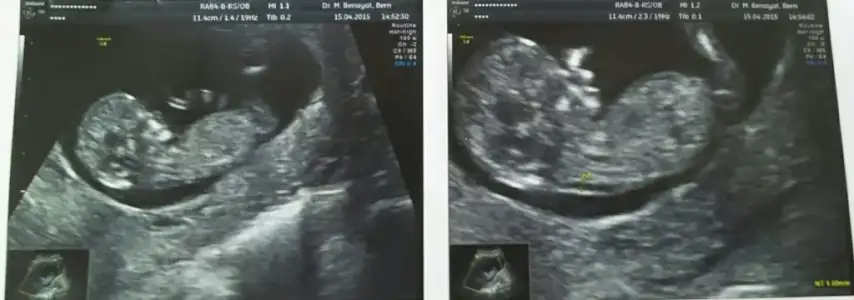

Kızlar ben geldim doktor %90 kız dedi buda foto..

Hayirli olsun canim ben sana neden yorum yaapmadiim ecaba genelde herkese yapiyorum .. gervekte bu resimde nubu paralel kiz oldu nekafar net .. bu fikirde guzel arkadaslar cinsiyeyi ogrenen fotosuda koyarsa hem dahada tecbubeleniriz..